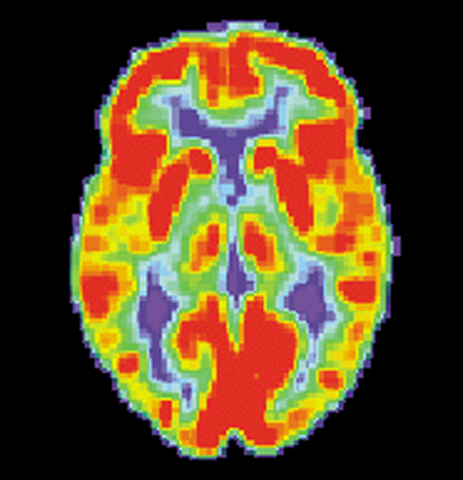

• PET Scan

PET Scan

The PET scan was tested by tracing chemical markers by nuclear magnetic resonance. PET stands for Position Emission Tomography.